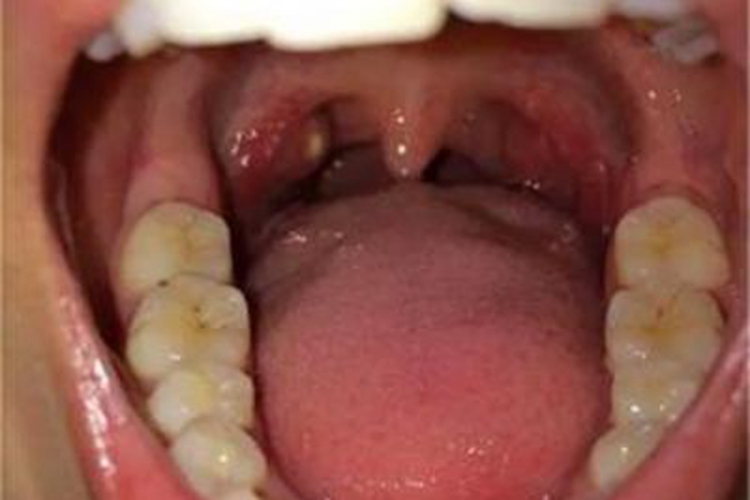

淋菌性咽炎可累及扁桃体,可表现为患者的双侧扁桃体轻微肿胀、充血,扁桃体表面有一块椭圆形的白色脓片。患者自觉咽喉痛,吞咽时疼痛加重。